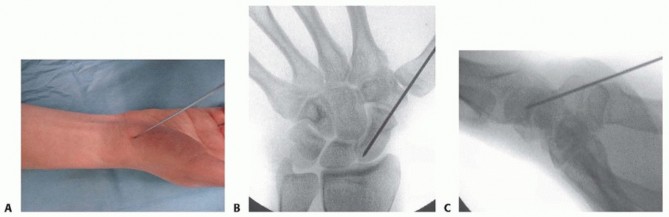

TECH FIG 3 • A. Reduction of a displaced scaphoid waist fracture using Kirschner wire joysticks. B. The Kirschner wire joystick technique for fracture reduction.(continued)

TECH FIG 3 •(continued)C. The guidewire is pulled volarly until it remains only in the distal fragment. The joysticks are then utilized to reduce the fracture. D. The guidewire is driven from volar to dorsal, transfixing the proximal fragment.